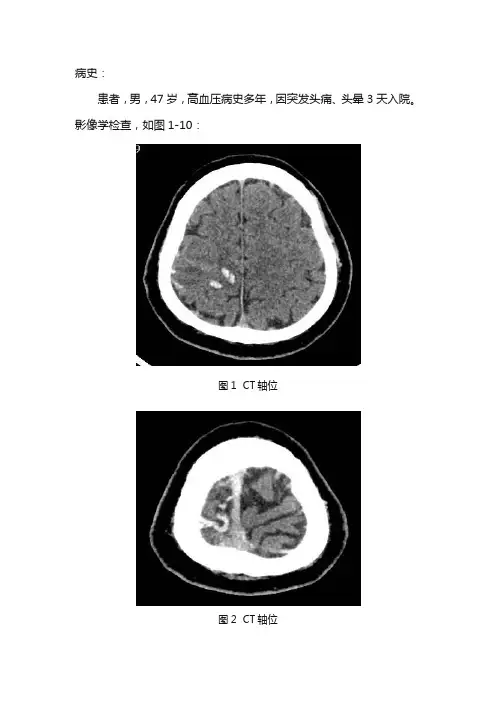

病史:患者,男,47岁,高血压病史多年,因突发头痛、头晕3天入院。

影像学检查,如图1-10:图1 CT轴位图2 CT轴位图3 T1WI轴位图4 T2WI轴位图5 FLAIR轴位图6 DWI图7 ADC图8 MRA图9 MRV图10 MRV基础解剖影像:图11-15为正常人颅脑主要层面T2WI轴位图片:图11图11为中脑层面,主要包括中脑(黄色箭头),前方为桥前池(棕色箭头),后方为第四脑室(蓝色箭头),颞叶(绿色箭头),小脑半球(白色箭头)。

影像描述:CT右侧双侧额顶叶皮质区可见条形高密度影,边界欠清。